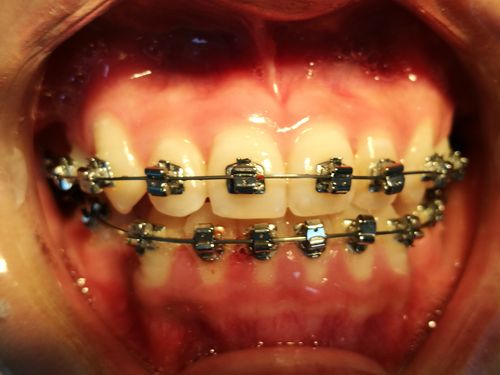

直丝弓矫治系统主要由托槽、弓丝、带环、结扎材料及辅助装置组成,托槽是核心部件,通常由金属或陶瓷材料制成,每个牙齿对应特定形态的托槽,其槽沟尺寸(如0.018英寸或0.022英寸)需与弓丝匹配;弓丝则根据矫治阶段选用不同材质和尺寸,初始排齐多用镍钛圆丝,调整咬合时使用不锈钢方丝;带环主要用于后牙,增强固位力;结扎丝或橡皮圈用于固定弓丝于托槽槽沟内。

直丝弓技术适用于多种错畸形,包括牙列拥挤、牙列稀疏、深覆合、深覆盖、反合(地包天)、开合及个别牙错位等,其治疗流程通常分为四个阶段:①初诊检查:通过口内检查、X光片(全景片、头颅侧位片)和模型分析,制定个性化方案;②矫治器粘接:将托槽精准粘接于牙齿表面,带环套于后牙;③主动加力阶段:定期更换弓丝(如从细镍钛丝到粗不锈钢丝),施加轻力引导牙齿移动,通常每4-6周复诊一次;④保持阶段:拆除矫治器后,佩戴保持器(如Hawley保持器或透明保持器)维持疗效,防止复发。